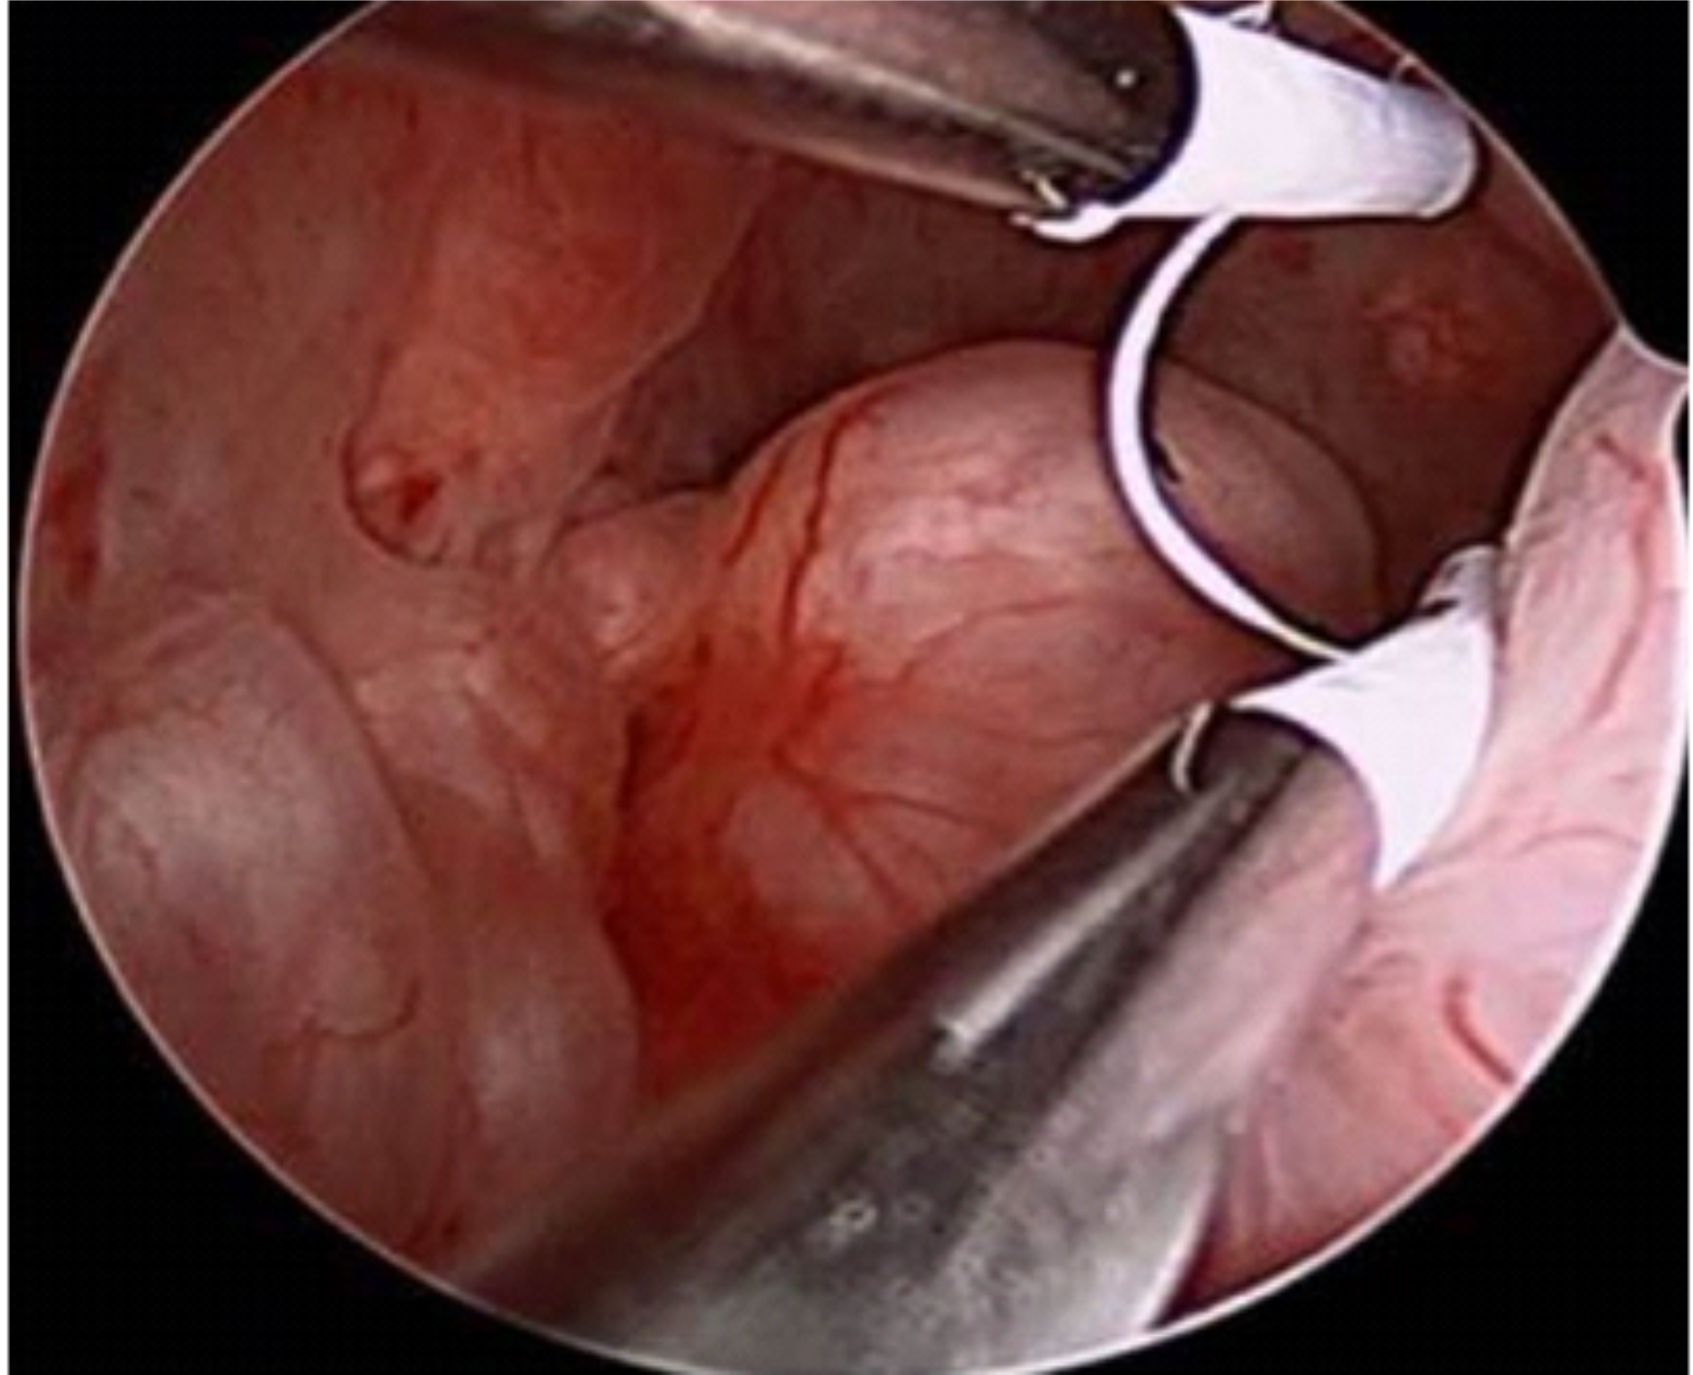

Segundo consenso da European Society of Human Reproduction and Embryology (ESHRE) e da American Society for Reproductive Medicine (ASRM), o padrão-ouro para diagnóstico de endometriose é a videolaparoscopia com inspeção direta da cavidade e visualização dos implantes, podendo ainda realizar-se biópsias para confirmação histopatológica.

A videoaparoscopia é um procedimento cirúrgico, feito em ambiente hospitalar sob anestesia geral. Uma microcâmera de vídeo é introduzida no abdomen por meio de uma incisão mínima na região do umbigo e assim temos uma visualização completa dos órgão pélvicos: útero, trompas, ovários, reto e bexiga, além de uma visão do abdome superior. Essa técnica permite então, o diagnóstico da endometriose, estadiar a extensão da doença e tratar simultaneamente as lesões. Como é um procedimento invasivo, em casos selecionados, pode-se tentar um tratamento empírico sem a realização da videolaparoscopia.

O quadro clínico é variável e sua intensidade não tem relação com a extensão das lesões. Exames de imagem geralmente ajudam pouco. O diagnóstico geralmente só é feito com a videolaparoscopia. A cirurgia é útil no diagnóstico e tratamento da doença que consiste na remoção de todos os focos.

Quanto à melhor abordagem cirúrgica, muitos serviços a realizam por laparotomia (cirurgia com corte usual do abdome, como na cesariana). Entretanto, o preconizado atualmente é a abordagem minimamente invasiva através da videolaparoscopia ou , mais atualmente, com auxílio da cirurgia robótica.

As vantagens da cirurgia videolaparoscópica quando comparada a laparotomia incluem: diminuição da permanência hospitalar, retorno mais rápido das pacientes às atividades do dia-a-dia (por exemplo, menos tempo longe trabalho), diminuição da morbidade (menor dor pós-operatória e com menos probabilidade de aderências e infecções da parede abdominal), diminuição da mortalidade e maior taxa de gravidez. A videolaparoscopia é preferível ainda à laparotomia porque proporciona a visualização de todo o abdômen e pelve com visão ampliada.